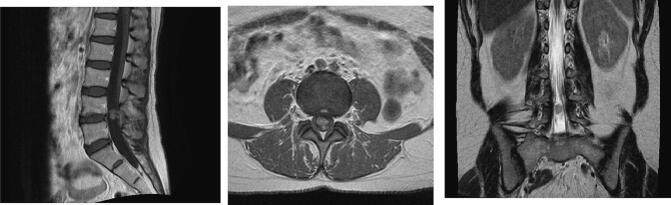

A 42-year-old female presented to our institution with a 9-month history of lower back pain. Her examination findings revealed a loss of right ankle jerk reflex. Magnetic resonance imaging (MRI) of her lumbosacral spine demonstrated an intradural, extramedullary tumor involving the cauda equina, at the L4/L5 level. The main differential diagnosis at this time was an ependymoma. An L4/5 laminectomy and resection of the cauda equina mass was scheduled. Intra-operatively, a mulberry - like mass was noted involving a single nerve root. A gross total resection was performed, with resolution of most of her symptoms. Histopathological diagnosis of a cavernous malformation was ascertained.

The accurate diagnosis of a cavernous malformation of the cauda equina was only suspected intra-operatively, following gross inspection. Cauda equina masses usually include myxopapillary ependymomas and schwannomas, making this vascular extramedullary lesion low on the possible differentials list. Very few cases have been published in modern literature.

Cavernous malformations of the cauda equina are an extremely uncommon, benign vascular malformation. These malformations have key characteristics on MRI that can aid its differentiation from other intradural lesions. However, because it is so rare, it does not usually make the list of differentials when considering likely extramedullary lesions.

一名42岁女性因下背部疼痛9个月就诊于我院。检查发现其右踝反射消失。腰骶椎磁共振成像(MRI)显示L4/L5水平硬膜内、髓外肿瘤累及马尾。此时主要的鉴别诊断为室管膜瘤。计划行L4/5椎板切除术及马尾肿块切除术。术中发现一个桑葚样肿块累及单一神经根。行肿瘤全切,其大部分症状得到缓解。术后病理诊断为海绵状血管畸形。

马尾海绵状血管畸形的准确诊断仅在术中肉眼检查后才被怀疑。马尾肿块通常包括黏液乳头型室管膜瘤和神经鞘瘤,使得这种血管性髓外病变在可能的鉴别诊断清单中排位靠后。现代文献中发表的病例极少。

马尾海绵状血管畸形是一种极其罕见的良性血管畸形。这些畸形在MRI上具有关键特征,有助于与其他硬膜内病变相鉴别。然而,由于其极为罕见,在考虑可能的髓外病变时,通常不会出现在鉴别诊断清单中。